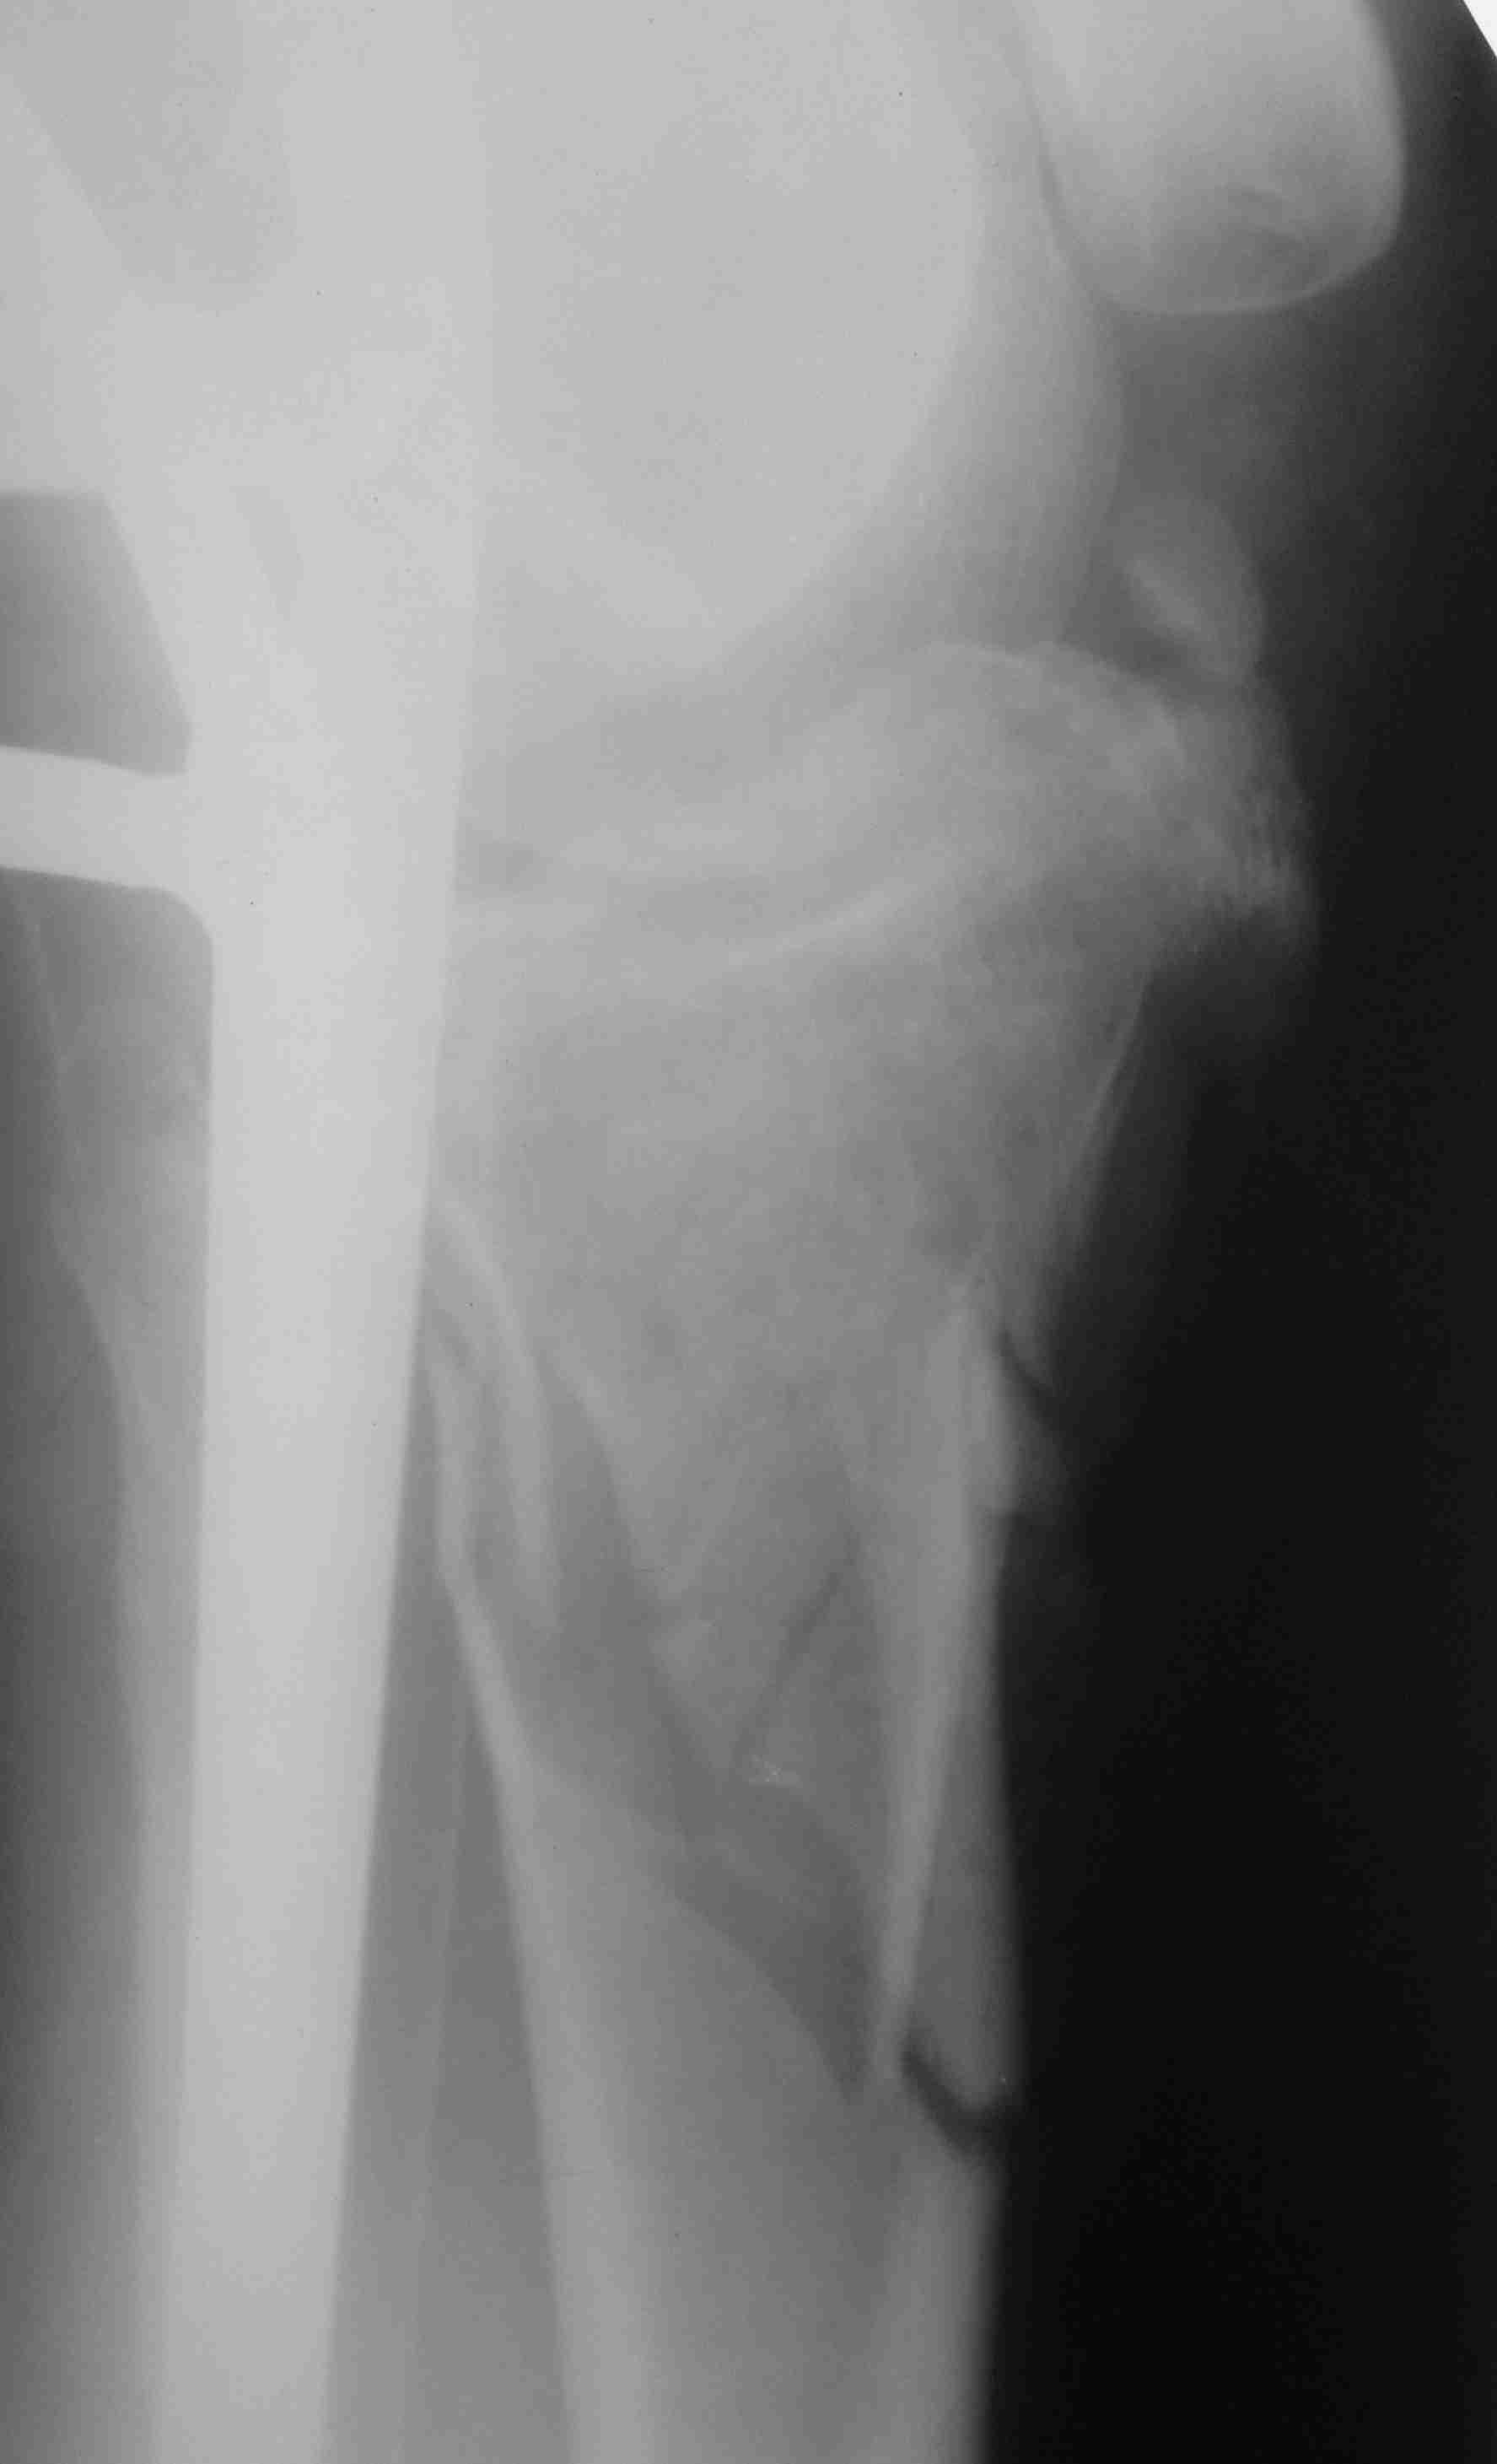

первым этапом сделали синтез задней стенки, дистракционный аппарат на ногу, снимки низкого качества, завтра постараюсь приложить нормальный рентген и КТ

Серия КТ сканов в аппарате

Голень-41-С3.1 - полный внутрисуставной и метафизарный оскольчатый перелом с доминантным повреждением наружного мыщелка, с импрессией центральной части плато. Первичная тактика полный респект по АО и ОТА. на фоне лигаметотаксиса выполнено КТ, которое четко детализирует повреждение и определяет дальнейшую тактику.